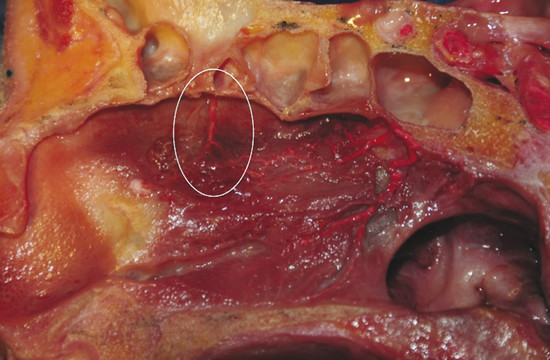

Blood supply of the nasal septum occurs through septal branches of the sphenopalatine artery. Here it anastomoses with branches of the palatine and labial arteries and septal branches of the anterior and posterior ethmoidal arteries; they are easily recognizable in the cranial portion of the septum area (Fig. 13‑1). An anatomical study on the arterial pattern of the nasal septum, traced by microdissection, demonstrated that AEAs were present in all cases, but the posterior ethmoidal arteries in some cases were absent. 1 These arteries, with the middle septal branch of the sphenopalatine artery and the superior labial branch of the facial artery, mainly contribute to the anastomotic triangle of the anterior septum. Only the posterosuperior area is vascularized by the posterior ethmoidal artery branches. 2 The ethmoidal artery originates from the terminal segment of the ophthalmic artery in the orbit cavity, a collateral branch of the internal carotid artery, and passes between the superior oblique and medial rectus muscle. The AEA then reaches the frontoethmoidal suture through the anterior ethmoidal foramen and enters into the anterior ethmoidal canal along with the anterior ethmoidal nerves. The artery crosses the ethmoid roof diagonally from posterolateral to anteromedial (Fig. 13‑2). AEA then divides at the lateral part of the cribriform plate of the ethmoid, giving off two or three branches to the mucosa of the cranial portion of the septum (Fig. 13‑3). Finally, they reach the olfactory cleft and supply terminal branches to the olfactory bulb and the meninges.

One must consider that the septal branches of the AEA are at the same level or just posterior to the septal projection of the axilla of the middle turbinate, as confirmed by a recent anatomical analysis, which showed that the average distance was 7.35 mm (range: 5.5–8.7 mm) and never superior to 1 cm. 3

Bleeding can be seen originating from a septal branch of the AEA, showing a close anatomic relation with the axilla of the middle turbinate (Fig. 13‑4). It is extremely important to consider this anatomical relation during harvesting the flap.